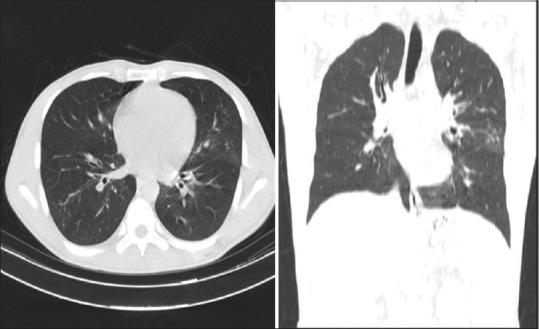

The Radiologic Society of North America (RSNA) divides patients into four sections: negative, atypical, indeterminate, and typical coronavirus disease 2019 (COVID-19) pneumonia based on their computed tomography (CT) scan findings. Herein, we evaluate the frequency of the chest CT-scan appearances of COVID-19 according to each RSNA categorical group.

According to the RSNA classification 87.8, 5.56, 4.44, and 2.22% of the patients were assigned as typical, indeterminate, atypical, and negative, respectively. The proportion of "atypical" patients was higher in the patients who had mediastinal lymphadenopathy and pleural effusion. Moreover, ground-glass opacity (GGO) and consolidation were more pronounced in the lower lobes and left lung compared to the upper lobes and right lung, respectively. While small nodules were mostly seen in the atypical group, small GGO was associated with the typical group, especially when it is present in the right lung and indeterminate group.

Regardless of its location, non-round GGO is the most prevalent finding in the typical group of the RSNA classification systems. Mediastinal lymphadenopathy, pleural effusion, and small nodules are mostly observed in the atypical group and small GGO in the right lung is mostly seen in the typical group.